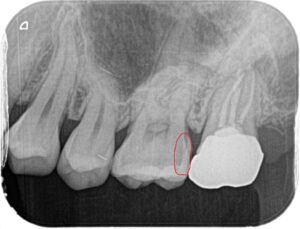

虫歯が隠れていそうな気配があったため小さいレントゲンを撮りました。

やっぱりありました!

写真の赤丸が虫歯の部分です。